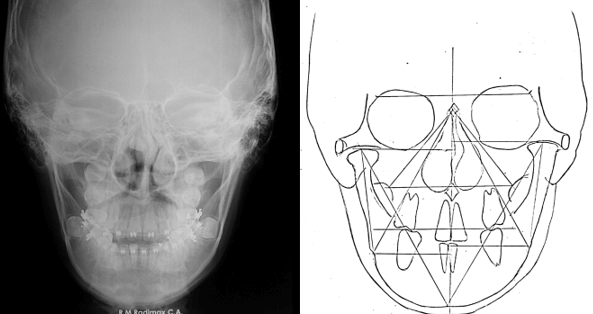

Radiografía Postero Anterior Inicial

Donde se puede evidenciar la marcada asimetría facial e hiperplasia condilar izquierda.